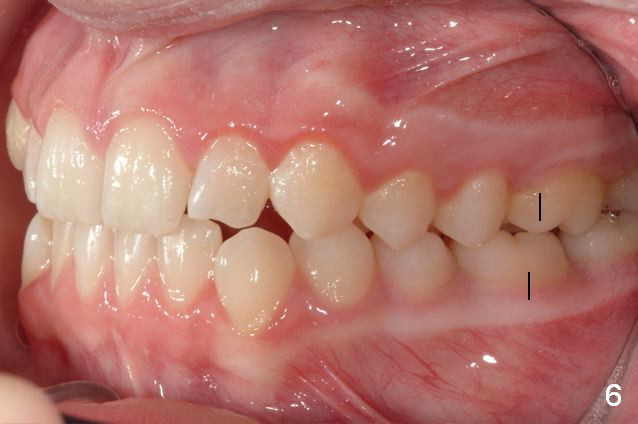

Unilateral Class II Malocclusion

The upper dental midline deviates to the left (Fig.2,4). Facial profile is normal (Fig.3). The right molar relationship is Class II (Fig.5), while the left one is normal or slightly Class III (Fig.6). How to treat?